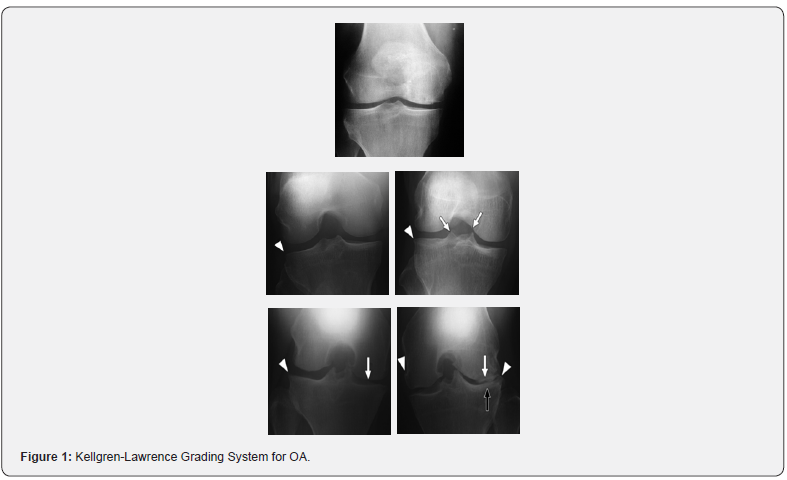

Kellgren-Lawrence Grading System for OA, 1957 [11]

(This is radiological assessment in which x-ray of both knees AP view in standing position are taken). (Figure 2)

Grade 0: Normal, no features.

Grade 1: Questionable presence of osteophytes/questionable presence of joint space narrowing / both.

Grade 2: Definite presence of osteophytes with possible joint space narrowing or definite mild joint space narrowing.

Grade 3: Definite moderate joint space narrowing (at least 50%) Osteophytes usually present, Cysts/sclerosis may be present.

Grade 4: Severe joint space narrowing with subchondral bone sclerosis and possible deformity of bone ends.

In osteoarthritis, there is increased blood flow and other changes that develop in the subchondral layer, subchondral sclerosis (increased bone density), subchondral cysts (fluid-filled sacs which extrude from the joint), and increased pressure within the bone -- all of which may cause osteoarthritis pain. There can be thickening of the joint capsule and the formation of osteophytes that may cause pain. There can be increased thickness of the synovium and mild inflammation at this site that causes pain (Figure 1).